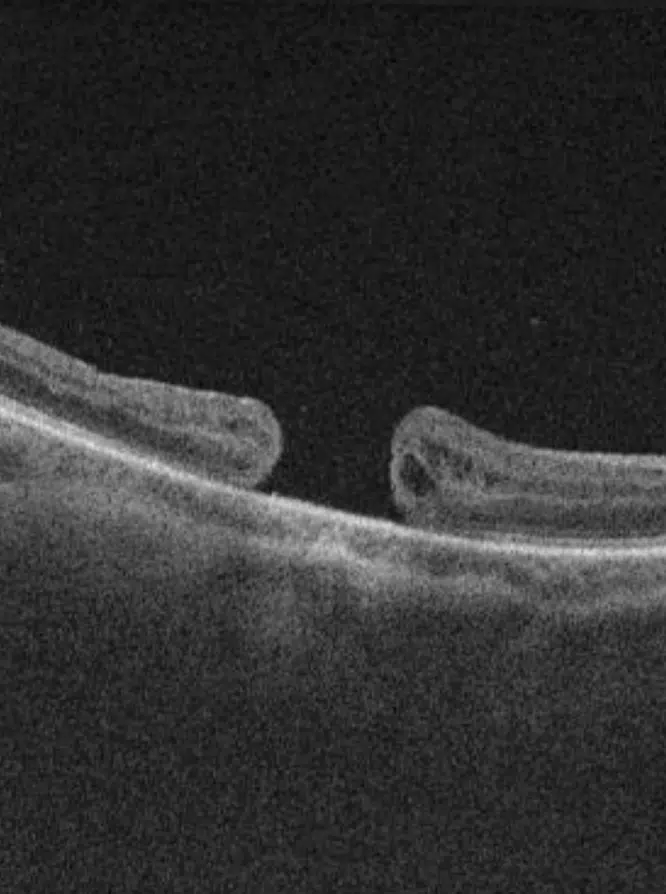

Trou maculaire

Un trou maculaire se produit lorsqu’une discontinuité de la macula perturbe la vision centrale. Une intervention chirurgicale comme la vitrectomie, souvent accompagnée d’une injection de gaz intraoculaire, permet dans la majorité des cas d’obtenir la fermeture du trou et d’améliorer la vision.